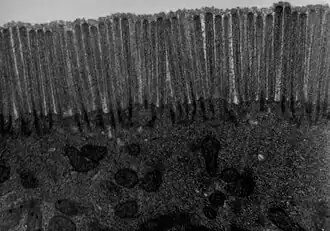

The interior surface of the jejunum—which is exposed to ingested food—is covered in finger–like projections of mucosa, called villi, which increase the surface area of tissue available to absorb nutrients from ingested foodstuffs. The epithelial cells which line these villi have microvilli. The transport of nutrients across epithelial cells through the jejunum and ileum includes the passive transport of sugar fructose and the active transport of amino acids, small peptides, vitamins, and most glucose. The villi in the jejunum are much longer than in the duodenum or ileum.

- The villi of the jejunum look like long, finger-like projections, and are a histologically identifiable structure.

Transmission electron microscope (TEM) image of human jejunum -